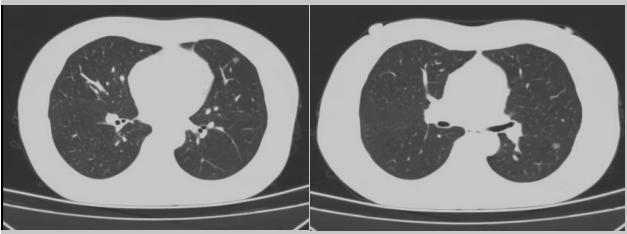

病例二:42歲的范女士,半年前體檢時(shí)發(fā)現(xiàn)雙側(cè)多發(fā)肺結(jié)節(jié),平時(shí)沒有什么不適。四個(gè)月后再次復(fù)查胸部CT,左上肺及下肺多發(fā)的磨玻璃結(jié)節(jié),其中下葉9mm的結(jié)節(jié)定為高危病灶。看到結(jié)果范女士坐不住了,多方打聽慕名找到了市二院院長王瑾,經(jīng)“肺結(jié)節(jié)MDT”團(tuán)隊(duì)會(huì)診后,決定手術(shù)治療。入院后,胸外科副主任醫(yī)師薛飛詳細(xì)與范女士溝通,并利用Mimics做好了術(shù)前肺部三維重建手術(shù)規(guī)劃,打消了范女士心中的顧慮。經(jīng)過前期充分準(zhǔn)備后,歷經(jīng)1小時(shí)30分,完成“胸腔鏡下左肺上葉舌段楔切及左肺下葉背段切除術(shù)”,術(shù)后病理檢查結(jié)果確診為左肺微浸潤性腺癌。在胸外科團(tuán)隊(duì)的悉心照顧下,患者術(shù)后恢復(fù)良好,一周后順利出院。